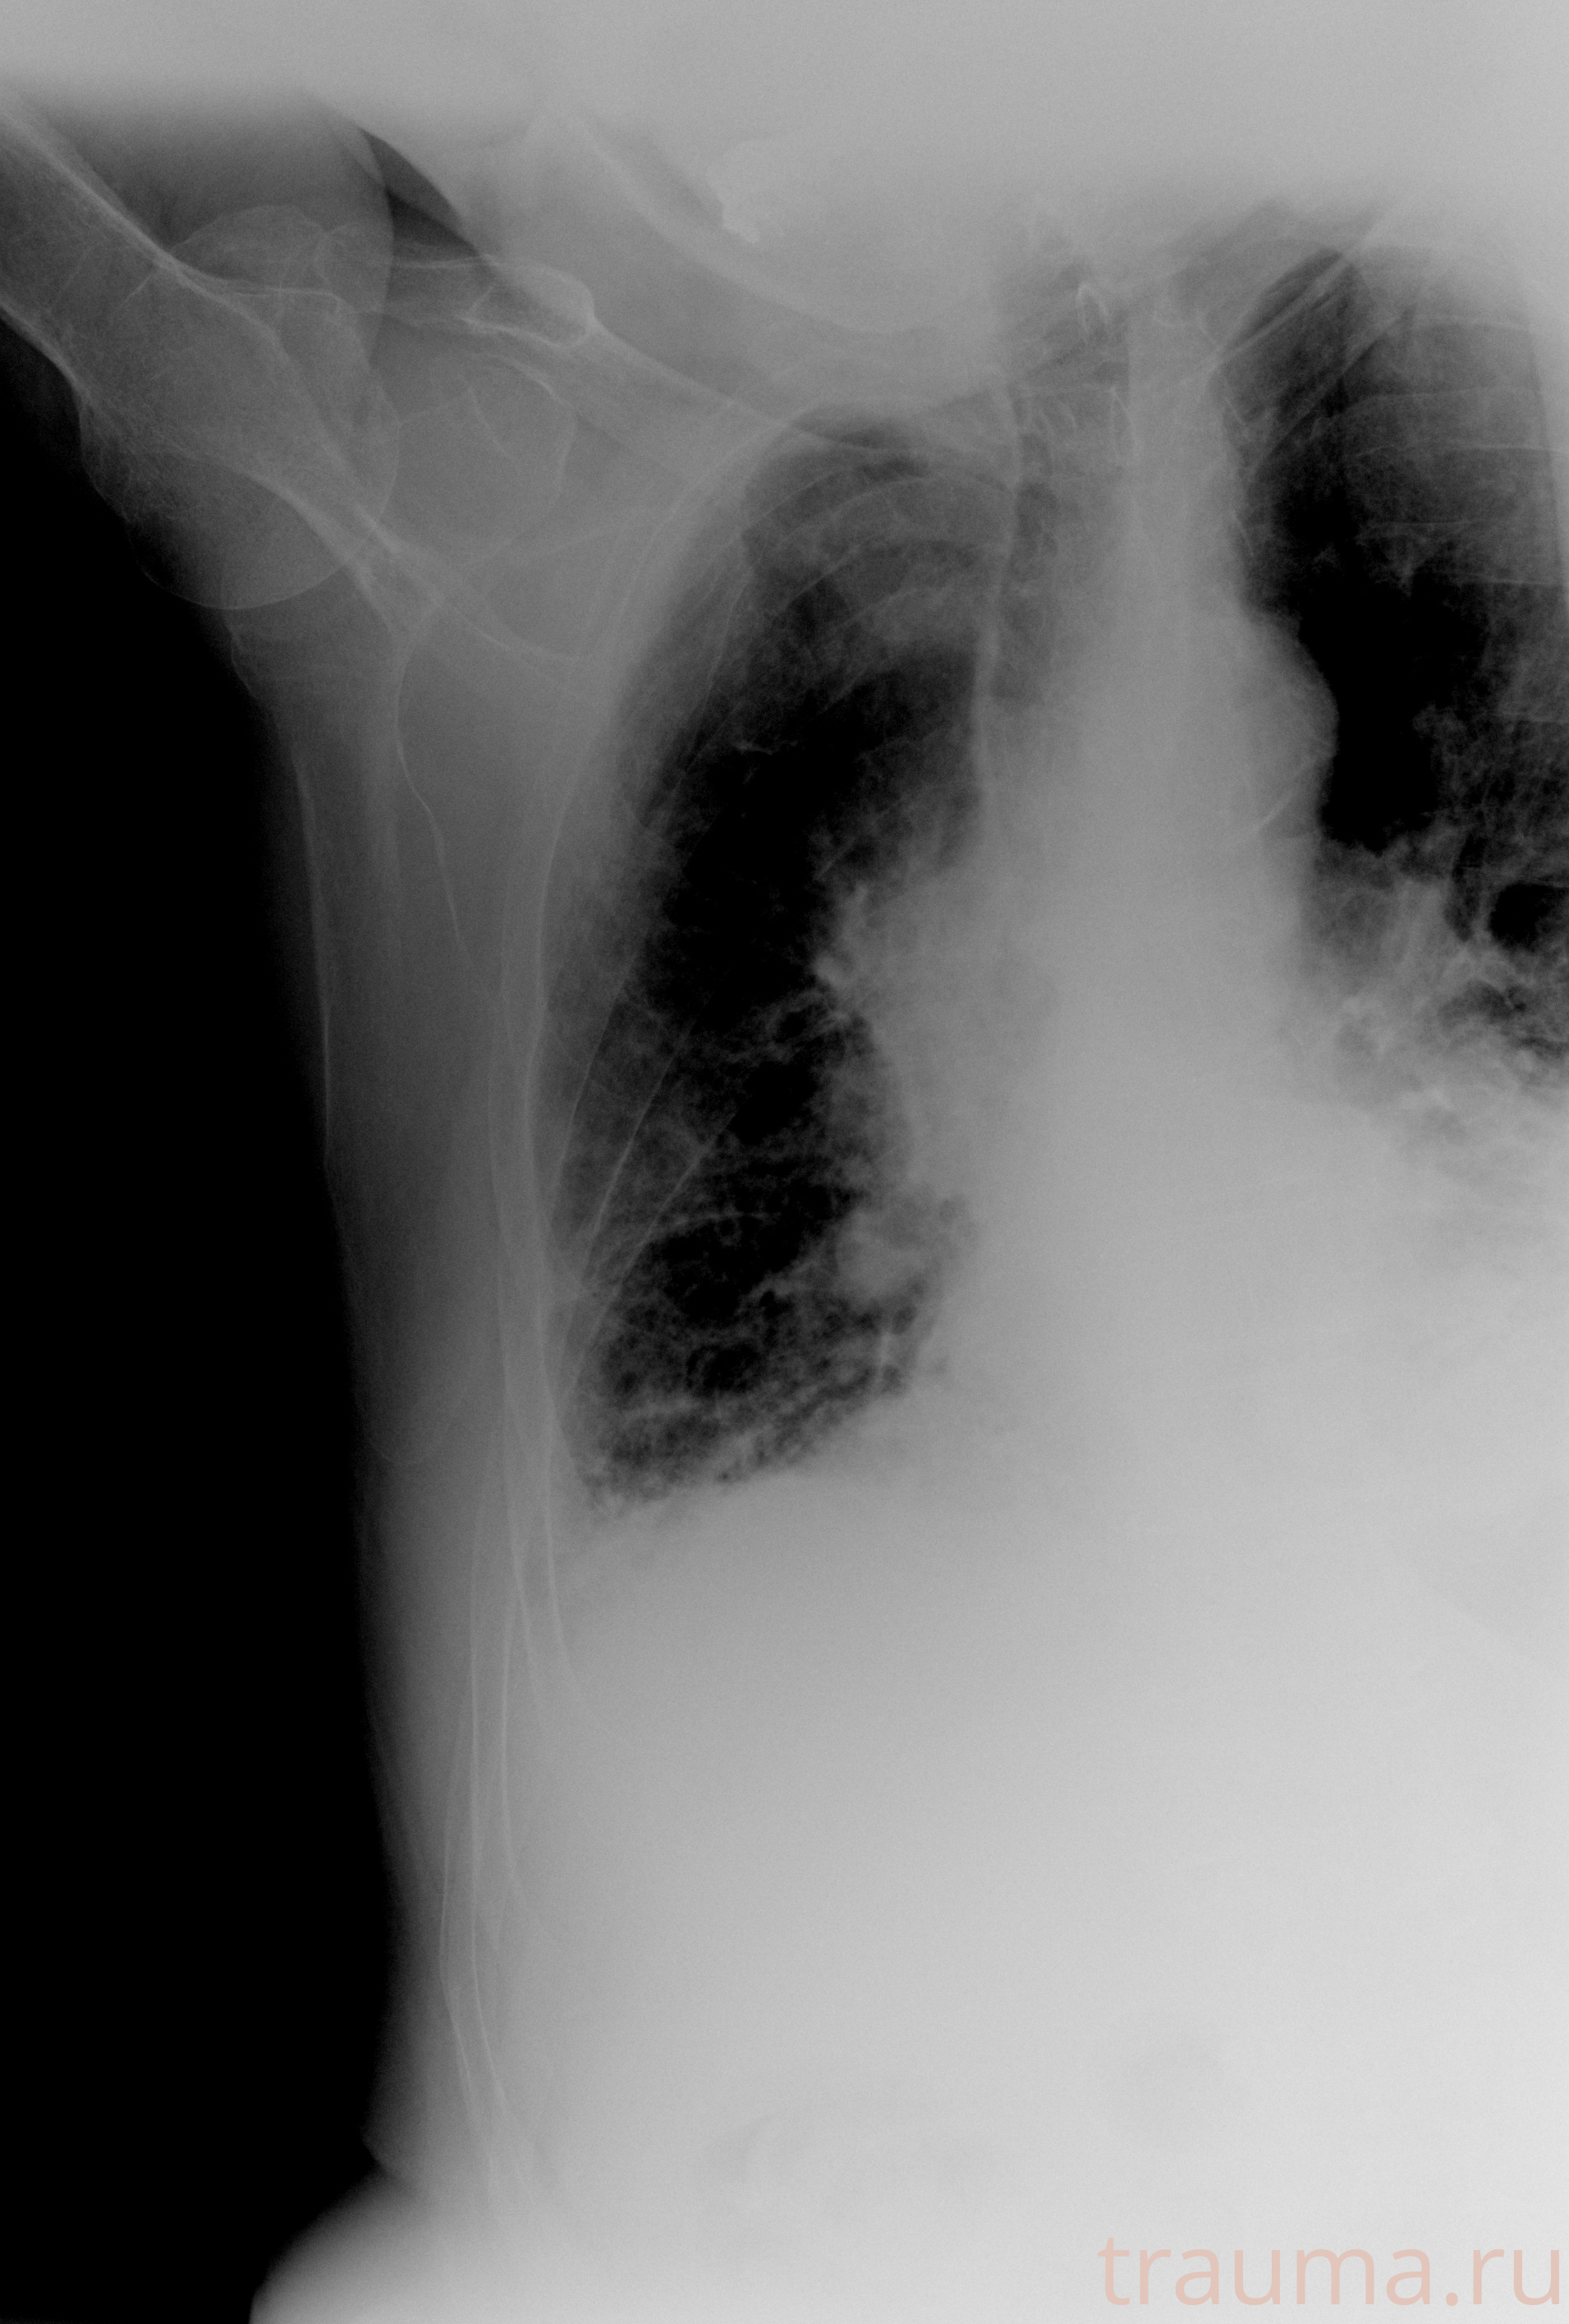

Рентген на дому: по вашему адресу приезжает врач-рентгенолог, травматолог-ортопед с мобильным рентгеновским аппаратом, проводит диагностику травмы или заболевания, делает необходимые рентгенограммы, дает рекомендации по дальнейшему лечению. Получить качественные снимки в домашних условиях возможно благодаря уникальной методике, разработанной МосРентген Центром для института  Склифосовского

при переломе шейки бедра и пневмонии от компании МосРентген Центр - партнера Института имени Склифосовского